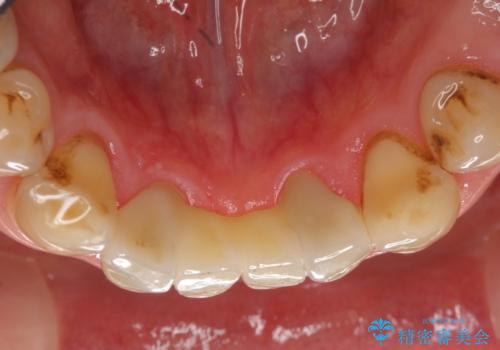

- 前歯の保険のブリッジが欠けてしまっているのを治したいとのことでした。

前装冠が剥がれていて、下の金属が見えてしまっていました。

保険のブリッジは入れてすぐ欠けてしまったのを長年使用していたとのことです。

かみ合わせもきつく、ジルコニアクラウンではセラミックでも欠けてしまいそうでした。

今回は、丈夫な欠けにくいフルジルコニア(ヴェレッツァ)クラウンでブリッジにすることにしました。